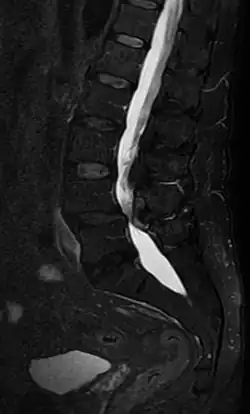

Die Diagnose kann durch bildgebende Verfahren wie Computertomographie (CT), Magnetresonanztomographie (MRT) oder Myelographie bestätigt werden.[3] Eine radiologisch gesicherte spinale Stenose erlaubt keine Aussage über das Ausmaß der Schmerzen.[4]